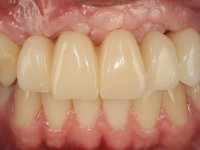

O paciente foi observado conjuntamente e a dúvida que surgiu de imediato foi se seria possível com a regeneração óssea a efectuar poder ser reabilitada naturalmente a zona das papilas interdentárias. Nesse sentido foi feito um enceramento de diagnóstico que contemplaria as duas hipóteses, utilizando ou não a cerâmica gengival. A confecção desse enceramento foi fundamental para expor ao paciente a dificuldade da reabilitação. O wax-up deu origem a um mock-up que foi aprovado pelo paciente e que simultaneamente serviu de guia imagiológica. O caso foi planificado cirurgicamente e realizada uma guia cirúrgica com que foram colocados os implantes. Após 10 semanas foi feita a 1ª impressão para confecção da ponte provisória. Foram criados os primeiros perfis de emergência na gengiva artificial e foi digitalizado o modelo. Por processo de CAD-CAM foi confeccionada uma ponte provisória aparafusada baseada no enceramento de diagnóstico. A ponte trabalhou durante 8 semanas os tecidos moles que foram fielmente copiados numa impressão com técnica de moldeira aberta. Os transferes foram individualizados com resina composta para copiarem fielmente os perfis de emergência criados pela ponte provisória. Confeccionado o modelo de trabalho definitivo, foi realizada uma infra-estrutura em zircónio seguindo a orientação do enceramento de diagnóstico. O assentamento da infra-estrutura foi testado em boca e simultaneamente foi novamente impressionados os tecidos moles com um silicone fluido. Nessa consulta foi feito o levantamento da cor. Os dentes 13 e 23 apresentavam uma saturação anormalmente forte que resolvemos não valorizar, optando por privilegiar a relação com o sector antero-inferior. Foi realizada uma nova gengiva artificial com a impressão que acompanhou a impressão de arrasto com a infra-estrutura. Após a colocação da cerâmica na infra-estrutura foram coladas as meso-estruturas. O trabalho final foi aparafusado lentamente permitindo a adaptação dos tecidos moles.